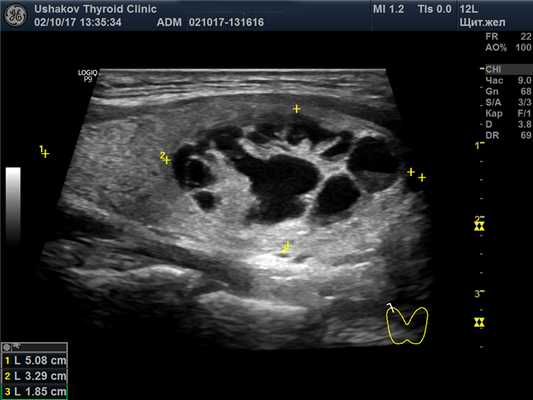

В правой доле щитовидной железы в центрально-каудальной части почти до её краев (в поперечной проекции) расположен овоидоподобной формы узел 22,9х20,7х33,1 мм (7,4 мл), окруженный по всему периметру чёткой гипоэхогенной границей-контуром, значительно неоднородный за счет множественных анэхогенных (жидкостных) участков (около 70% от объёма узла), преимущественно с чёткими границами в виде узких перегородок с изо- и гиперэхогенной (фиброзной) тканью и изоэхогенной тканью по периметру узла; при ЭДК заметно примыкание к узлу с кранио- и каудальной сторон магистральных сосудов, и умеренный кровоток по части периметра и мало интенсивный внутри узла (в перегородках); при эластографии SR 2,8 (3,3 - в обл. некоторых перегородок). Вне узла ткань изоэхогенная, почти однородная; в краниальном полюсе 21,2х15х15,1 мм (2,3 мл), а также медиально. В режиме ЦДК и ЭДК кровообращение в этой ткани в малой степени усилено.

Рис. 27.7. Пример 1. (правая доля, продольная проекция).

Структура узла представлена крупными сегментами, в центре которых – кистозные участки, почти повторяющие форму сегментов узла. Жидкостная (анэхогенная) часть узла преобладает над тканевой.

Рис. 27.11. Пример 1. (правая доля, продольная проекция).

За узлом в доле – макроструктурно полноценная ткань.

Но ткань расположена ещё и вокруг узла (больше с медиальной стороны). Поэтому разница объёма доли и узла (11,4-7,4) показывает 4 мл, что составляет 35% от величины доли и также указывает на субтотальнодолевой узловой зоб.

Узловой процесс. Узел в правой доле является крупным, т.к. его объём превышает 4 мл. Большая часть этого объёма состоит из жидкости. Поэтому важно указать величину жидкой части внутри узла.

Обратите внимание на сегментарное устройство ткани узла. Весь узел состоит из средней величины сегментов, внутри которых за счёт деструкции ткань распалась и накопилась жидкость. Это естественное стадийное изменение. Величина и распространённость деструкции в узле (почти все его сегменты имеют признаки значительного разрушения (рис. 27.11)) указывают на стадию значительного истощения.